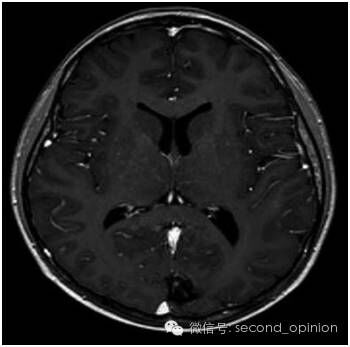

患者处于肝癌晚期,肝癌病灶巨大且有脑转移,国内医疗机构不能实施外科手术治疗。经全球肿瘤医生网请意大利humanitas医院专家组远程咨询,患者于2014年11月10日赴意大利进行EDGE速锋刀无创手术治疗。先后对肝脏肿瘤和脑转移瘤进行EDGE治疗,在医院共治疗8天。每个肿瘤每天治疗1次,每次治疗时间约10分钟左右,肝脏肿瘤共治疗6次,脑肿瘤治疗4次。患者手术过程中无任何不适,每次治疗后正常回公寓休息。半年后,患者身体状态良好,体重明显增加。影像检查报告显示肝脏的巨大肿瘤被彻底清除,脑部肿瘤几乎完全消除,且没有复发。生化检查结果表明肝功能未见异常。

脑转移瘤治疗前3cm

脑转移瘤治疗后基本消失